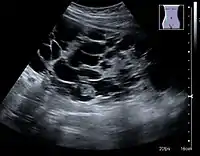

Renal cyst as seen on abdominal ultrasound